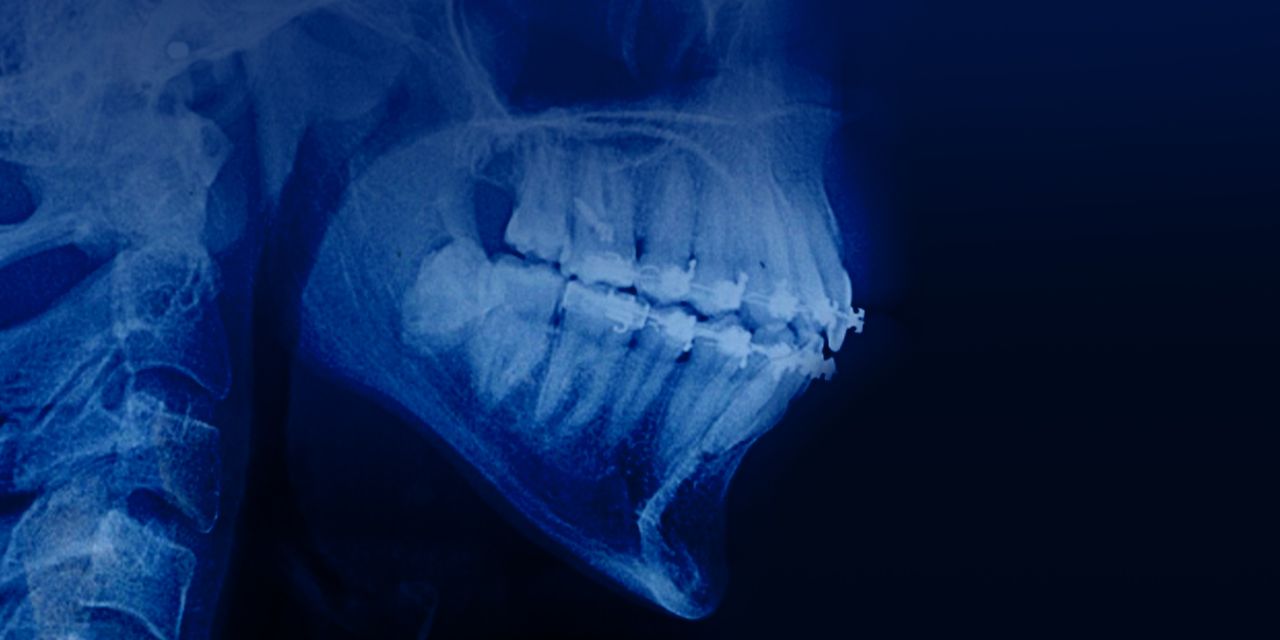

Distalización molar inferior: tratamiento de casos complejos de aglomeración y oclusión mesial sin extracción

– La distalización secuencial molar inferior se utiliza en caninos inferiores mesialmente inclinados y fuera de arco ayudando evitar reducción de esmalte interproximal o extracción premolar inferior.

– Tratamiento de casos complejos de oclusión mesial combinados con oclusión abierta.

– Obtención del espacio para la colocación del implante con la distalización molar inferior.

– El control de anclaje del arco inferior: alineadores + elásticos del clase III.

– La evaluación comparativa del uso de la distalización secuencial del arco inferior con el sistema invisalign y del tratamiento tradicional.